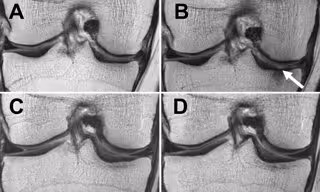

El equipo de investigación estudió la asociación entre la pérdida de peso y la progresión de los cambios de cartílago en la resonancia magnética durante un periodo de 48 meses en 640 pacientes con sobrepeso y obesidad (índice de masa corporal mínimo de 25 kg/m2) que presentaban factores de riesgo de artrosis o imágenes de resonancia magnética con evidencia de artrosis de leve a moderada.

Los investigadores no sólo detectaron que la pérdida de peso frenó la degeneración del cartílago articular, también vieron cambios en los meniscos, que son las almohadillas de fibrocartílago en forma de media luna que protegen y amortiguan la articulación.

"El hallazgo más emocionante de nuestra investigación fue que no sólo vimos degeneración más lenta en el cartílago articular, sino que detectamos que los meniscos se degeneraron mucho más lento en personas con sobrepeso y obesas que perdieron más del 5 por ciento de su peso corporal y que los efectos fueron más fuertes en personas con sobrepeso y en individuos con pérdida de peso sustancial", afirma Gersing.